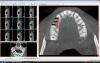

Тимур86 Опубликовано 28 октября, 2012 Поделиться Опубликовано 28 октября, 2012 планируются импланты в области 14,15.Alfa bio 3.75.Расстояние между зубом и имплантом с обеих сторон 1.5-1.7,между имплантами 2.7.... Ссылка на комментарий